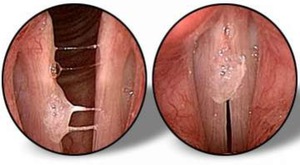

После пройденных заболеваний защитные силы организма ослабевают и уже не могут полностью сопротивляться инфекционным возбудителям. На изображении ниже можно рассмотреть, как выглядят голосовые связки при ларингите:

На четвертом и шестом изображениях демонстрируется бактериальный ларингит, который влияет на голосовые связки.